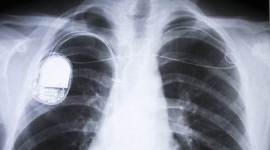

Millions of people rely on pacemakers, defibrillators and other live-saving implantable devices powered by batteries that need to be replaced every five to 10 years.